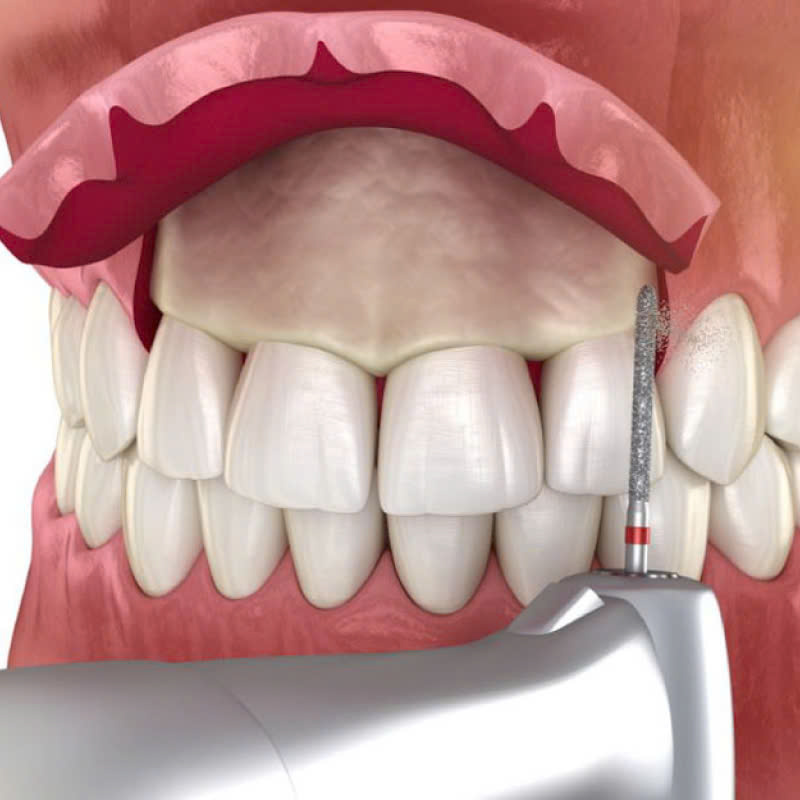

- Phẫu thuật

Bác sĩ sẽ thực hiện phẫu thuật theo phác đồ đã được lên kế hoạch, sử dụng dụng cụ chuyên dụng để điều chỉnh kích thước và hình dạng của xương ổ răng.